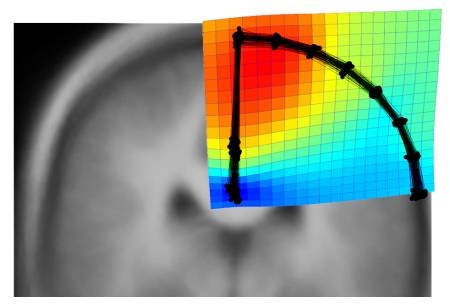

También se ha evaluado con modelos espaciales si la forma y la extensión de estos surcos internos afectan exteriormente la geometría del cerebro, concluyendo que “el tamaño del precúneo puede influir en la forma cerebral, pero la variación interna de sus pliegues no parece producir cambios secundarios de la superficie de la corteza”, señala Emiliano Bruner.

Los resultados sugieren que a nivel paleoneurológico, es decir a nivel de la forma cerebral en los fósiles, es posible detectar indirectamente variaciones en el tamaño general de algunas áreas de la corteza profunda (como el precúneo o el surco intraparietal), gracias a los efectos sobre la organización espacial del cerebro, “pero probablemente no se puedan detectar cambios más sutiles de sus proporciones internas y de sus surcos.”, declara Bruner.